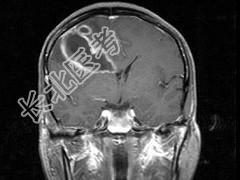

- 单项选择题男,49岁, 头痛、左侧肢体不能活动1周,PE: 左上下肢肌力O级,根据所提供图像, 最可能的诊断是 ( )

A、(右额顶)脑结核

B、(右额顶)脑转移瘤

C、(右额顶)脑脓肿

D、(右额顶)脑膜瘤

E、(右额顶)胶质瘤